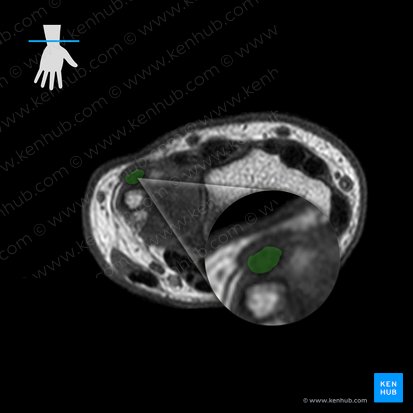

Neurovasculature

Last but not least, let’s see how the neurovasculature changes distally along the radiocarpal joint. Luckily for you, it stays almost the same with two exceptions. The ulnar artery and nerve travel within a hyperintense ulnar canal (Guyon’s canal). This passageway is located superficially to the common flexor tendon sheath of hand, sharing a border with the latter. The last remaining difference is the appearance of the superficial palmar branch of the radial artery. This is also located within the hyperintense subcutaneous tissue on the radial aspect of the radiocarpal joint (right side of image), but more superficial than its parent blood vessel.